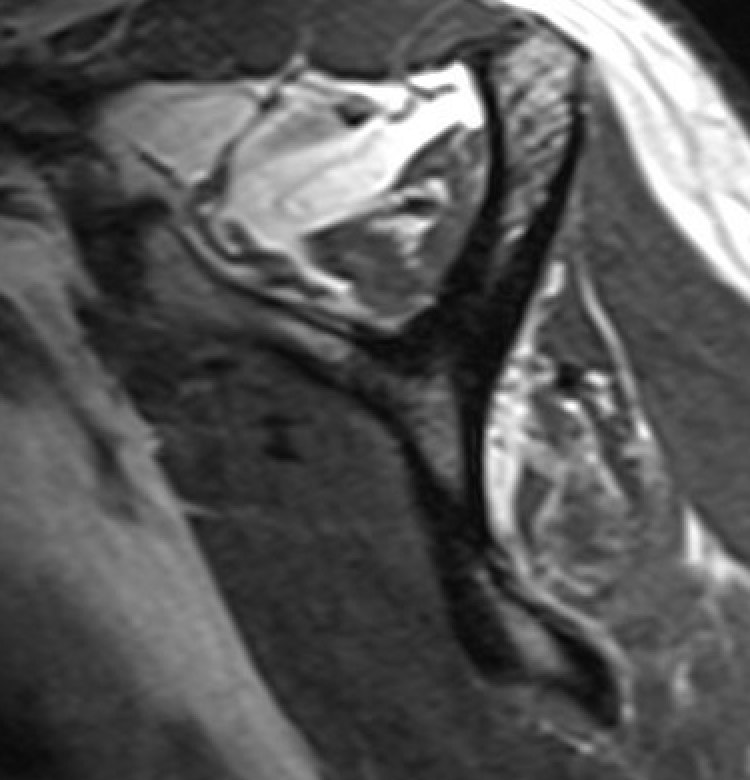

Full thickness rotator cuff tears

Partial bursal sided tear Partial articular sided tears

Small full thickness rotator cuff tear of supraspinatus - retracted to footprint

Large full thickness tear of supraspinatus and infraspinatus tendon - retracted to midhumeral head

Massive rotator cuff tear of the supraspinatus and infraspinatus tendon - retracted to glenoid